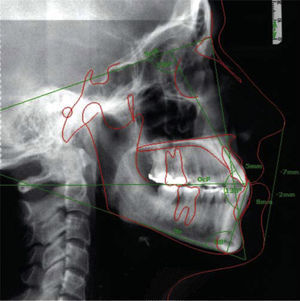

In the cephalometric analysis she was a skeletal class III, mesocephalic, with a concave profile, neutral growth and lower lip protrusion (Figure 1). In the panoramic radiograph she presented 28 erupted permanent teeth, loss of alveolar crests and a root-crown ratio of 3:1 (Figure 2).

In the final cephalometry and in the superimposition, the skeletal changes were: initial facial depth: 94°, final: 92°; initial maxillary depth: 94°, final 95.4°; initial convexity: 0mm, final: 3.2mm; initial facial axis: 89°, final: 92.6°; initial Gn-GN/L1: 88°, final: 89°; initial SN/ U1: 100°, final 115° (Figure 13). It may be observed that a conservative treatment was performed since no surgical procedure was needed to correct the skeletal problem in addition to controlling periodontal health and improving the patient's esthetic conditions. However in order to achieve these results, the upper incisors were proclined (Figure 14).